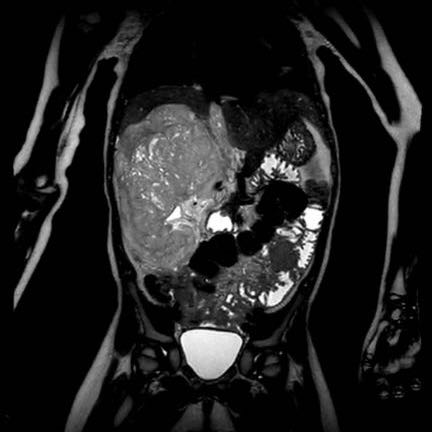

Ca lâm sàng 1

Hình ảnh chuỗi xung T2W mặt phẳng coronal cho thấy một khối u không đồng nhất ở thận trái với các thành phần nang nhỏ.

Khối u ngấm thuốc kém hơn so với phần nhu mô thận bình thường còn lại ở ngoại vi.

Các thành phần đặc của khối u cho thấy hạn chế khuếch tán rõ rệt (mũi tên).

Đây là u Wilms ở bé trai năm tuổi. Hóa trị tiền phẫu được thực hiện theo phác đồ Umbrella của SIOP-RTSG, sau đó tiến hành cắt thận.